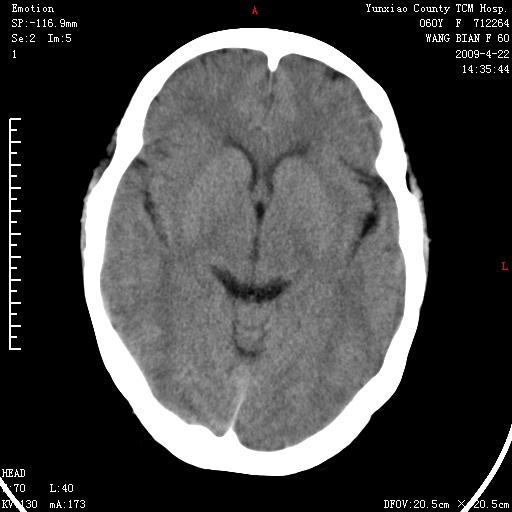

1、头颅未见明显异常。

2、左肾囊肿。

1、头颅未见明显异常。2、左肾囊肿可能。建议增强

1、枕骨蛛网膜粒压迹。2、左肾囊肿可能。建议增强

头颅未见明显异常。左肾囊肿。

1)枕骨蛛网膜粒压迹。2)左肾囊肿可能。